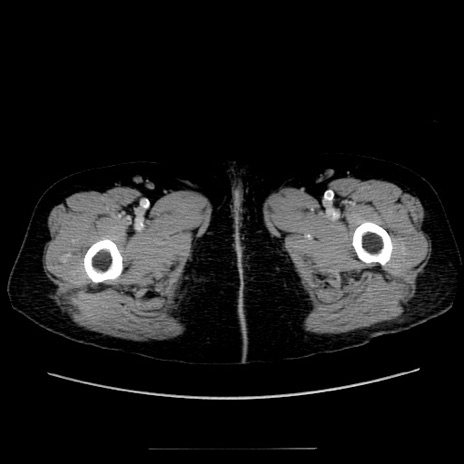

症例5(横断像)

【症例】70歳代女性

【主訴】お腹が張る

【現病歴】1週間くらい前から腹部膨満の自覚あり。昨日夜から増悪したため、本日救急外来受診。

【身体所見】意識清明、BT 36.5℃、BP 165/106mmHg、HR 80bpm、SpO2 98%、腹部:膨満、軟、自発痛・圧痛なし、触診にて不快感あり、腸蠕動音:減弱

【データ】WBC 12600、CRP 1.04